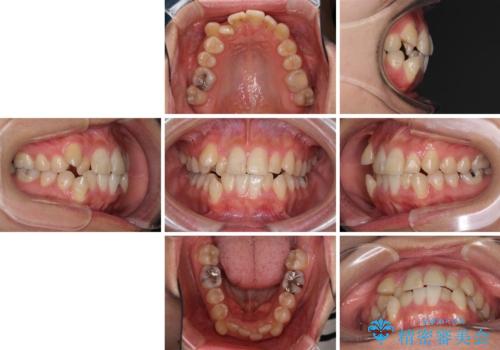

- 上下の八重歯を気にして来院された患者様です。

八重歯の後ろの歯を1歯抜歯し、補助装置(リンガルアーチ)を用いて八重歯の位置を改善し、その後インビザラインにより矯正治療を行うこととしました。

右側のみ上下小臼歯を抜歯したため、上下の正中が右にずれてしまう可能性があります。

また、元々右側は上下が咬み合っていないため、矯正をしても咬み合わないことも考えられました。

治療期間はかかりましたが、正中も合い、綺麗な仕上がりとなりました。